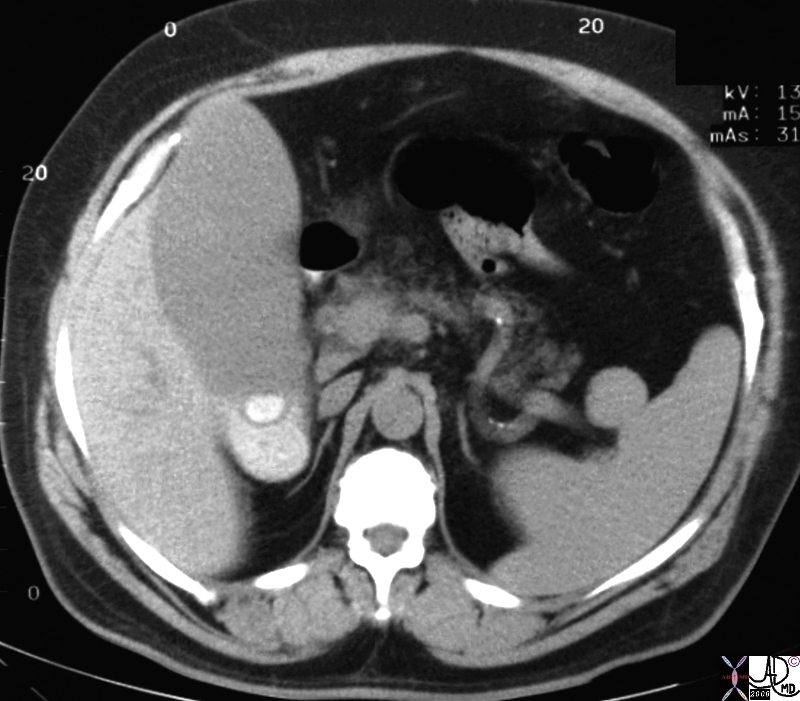

Accessory spleens are small, additional spleens that can develop alongside the primary spleen. They contribute to the body’s immune response and can be found in various locations within the abdominal cavity. Understanding their function and significance can aid in diagnosing certain medical conditions and enhance treatment strategies.

What are accessory spleens?

Accessory spleens are small, additional spleens that can develop in the body, typically near the primary spleen.

How common are accessory spleens?

Accessory spleens are relatively common, occurring in about 10% of the population.

Can accessory spleens cause health problems?

Generally, accessory spleens do not cause health issues, but in rare cases, they can complicate certain medical conditions.